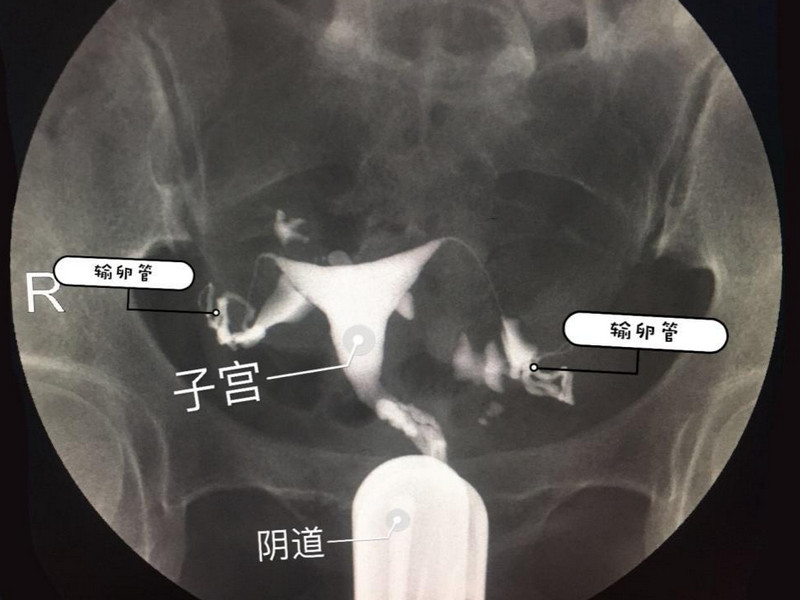

一般输卵管应呈水平走行或稍向下行至壶腹部时又稍向上行或在子宫体部两侧弯曲绕行,从内到外由细到粗,自然柔软。造影剂经伞部流出后向下进入子宫直肠陷凹呈横行条纹影,两侧卵巢呈对称性圈形负影,造影剂在卵巢附近呈波浪状或弧线形阴影称“腹膜涂抹”。推荐造影应在透视下动态实时观察,并且必须要有弥散相图片。

• 3.在子宫和输卵管中注入导管,避免造影剂外溢,待造影剂流入子宫和输卵管后,在x线透视下观察造影剂流经子宫腔及输卵管的情况。24小时后,在相同的地点再拍一次。